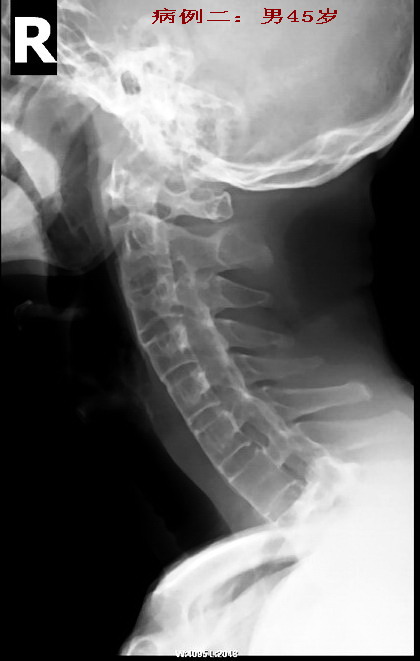

病例二:强直性脊椎炎晚期病例。

男性45岁,患者已有明显的颈部强直症状。从骶髂关节上行至颈椎均呈典型改变(腰椎侧位片已遗失.没有也无所谓)。

竹节状。典型